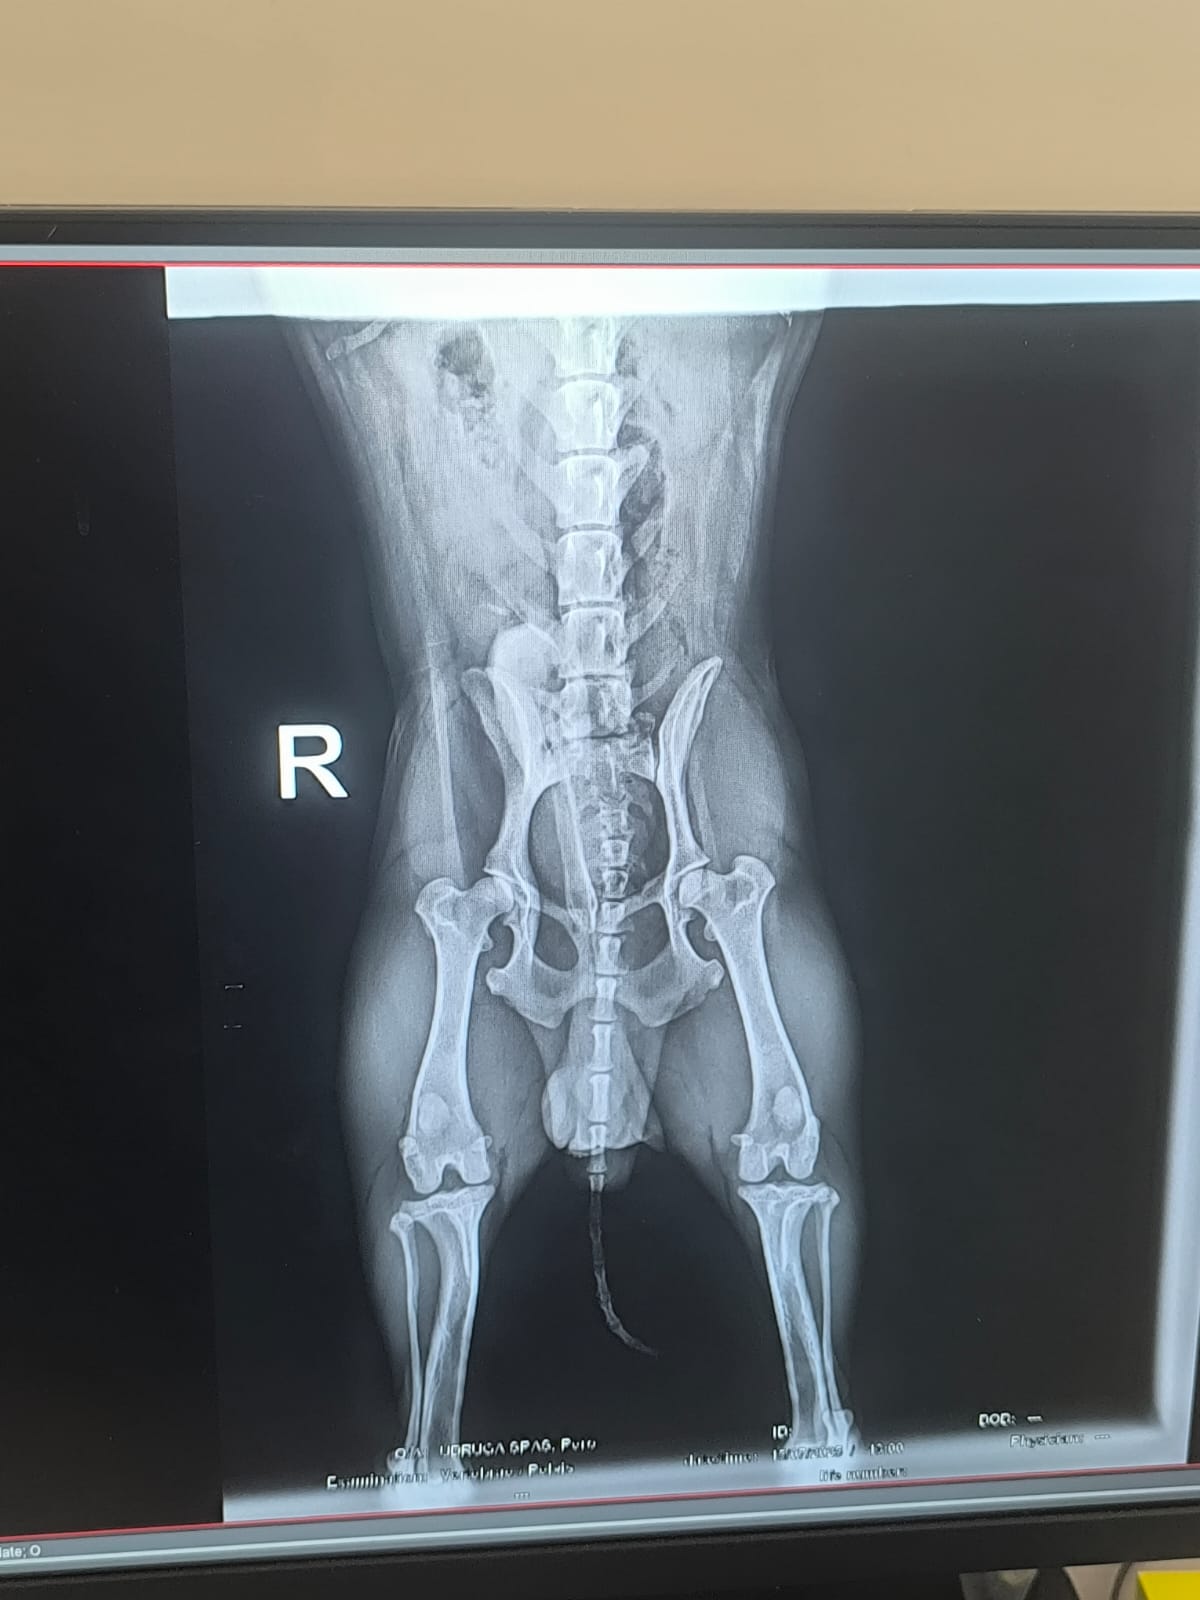

Fenix hatte bereits im Asyl einen schweren Start ins Leben. Schwer verletzt wurde er in Kroatien gefunden, seine Hinterbeine waren gelähmt. Eine Pflegefamilie nahm ihn auf und schenkte ihm die Chance auf medizinische Hilfe und ein neues Leben. In Deutschland wurde Fenix schließlich an der Wirbelsäule operiert. Nach dieser belastenden…